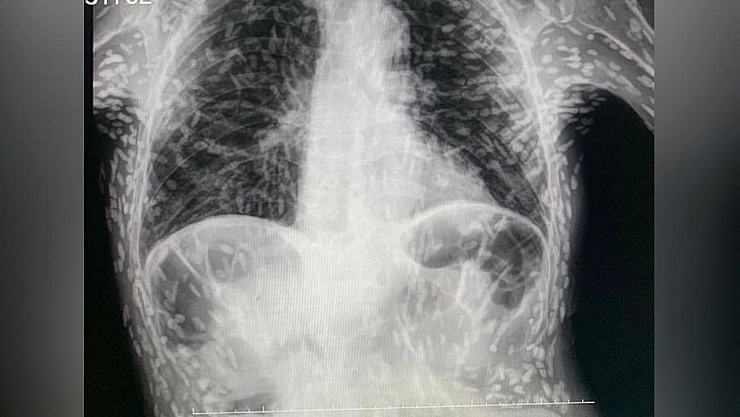

Hastanın röntgeninde yüzlerce beyaz nokta tespit edildi. Bu beyaz noktaların parazitlerin kireçlenmiş kalıntıları olduğu ortaya çıktı.